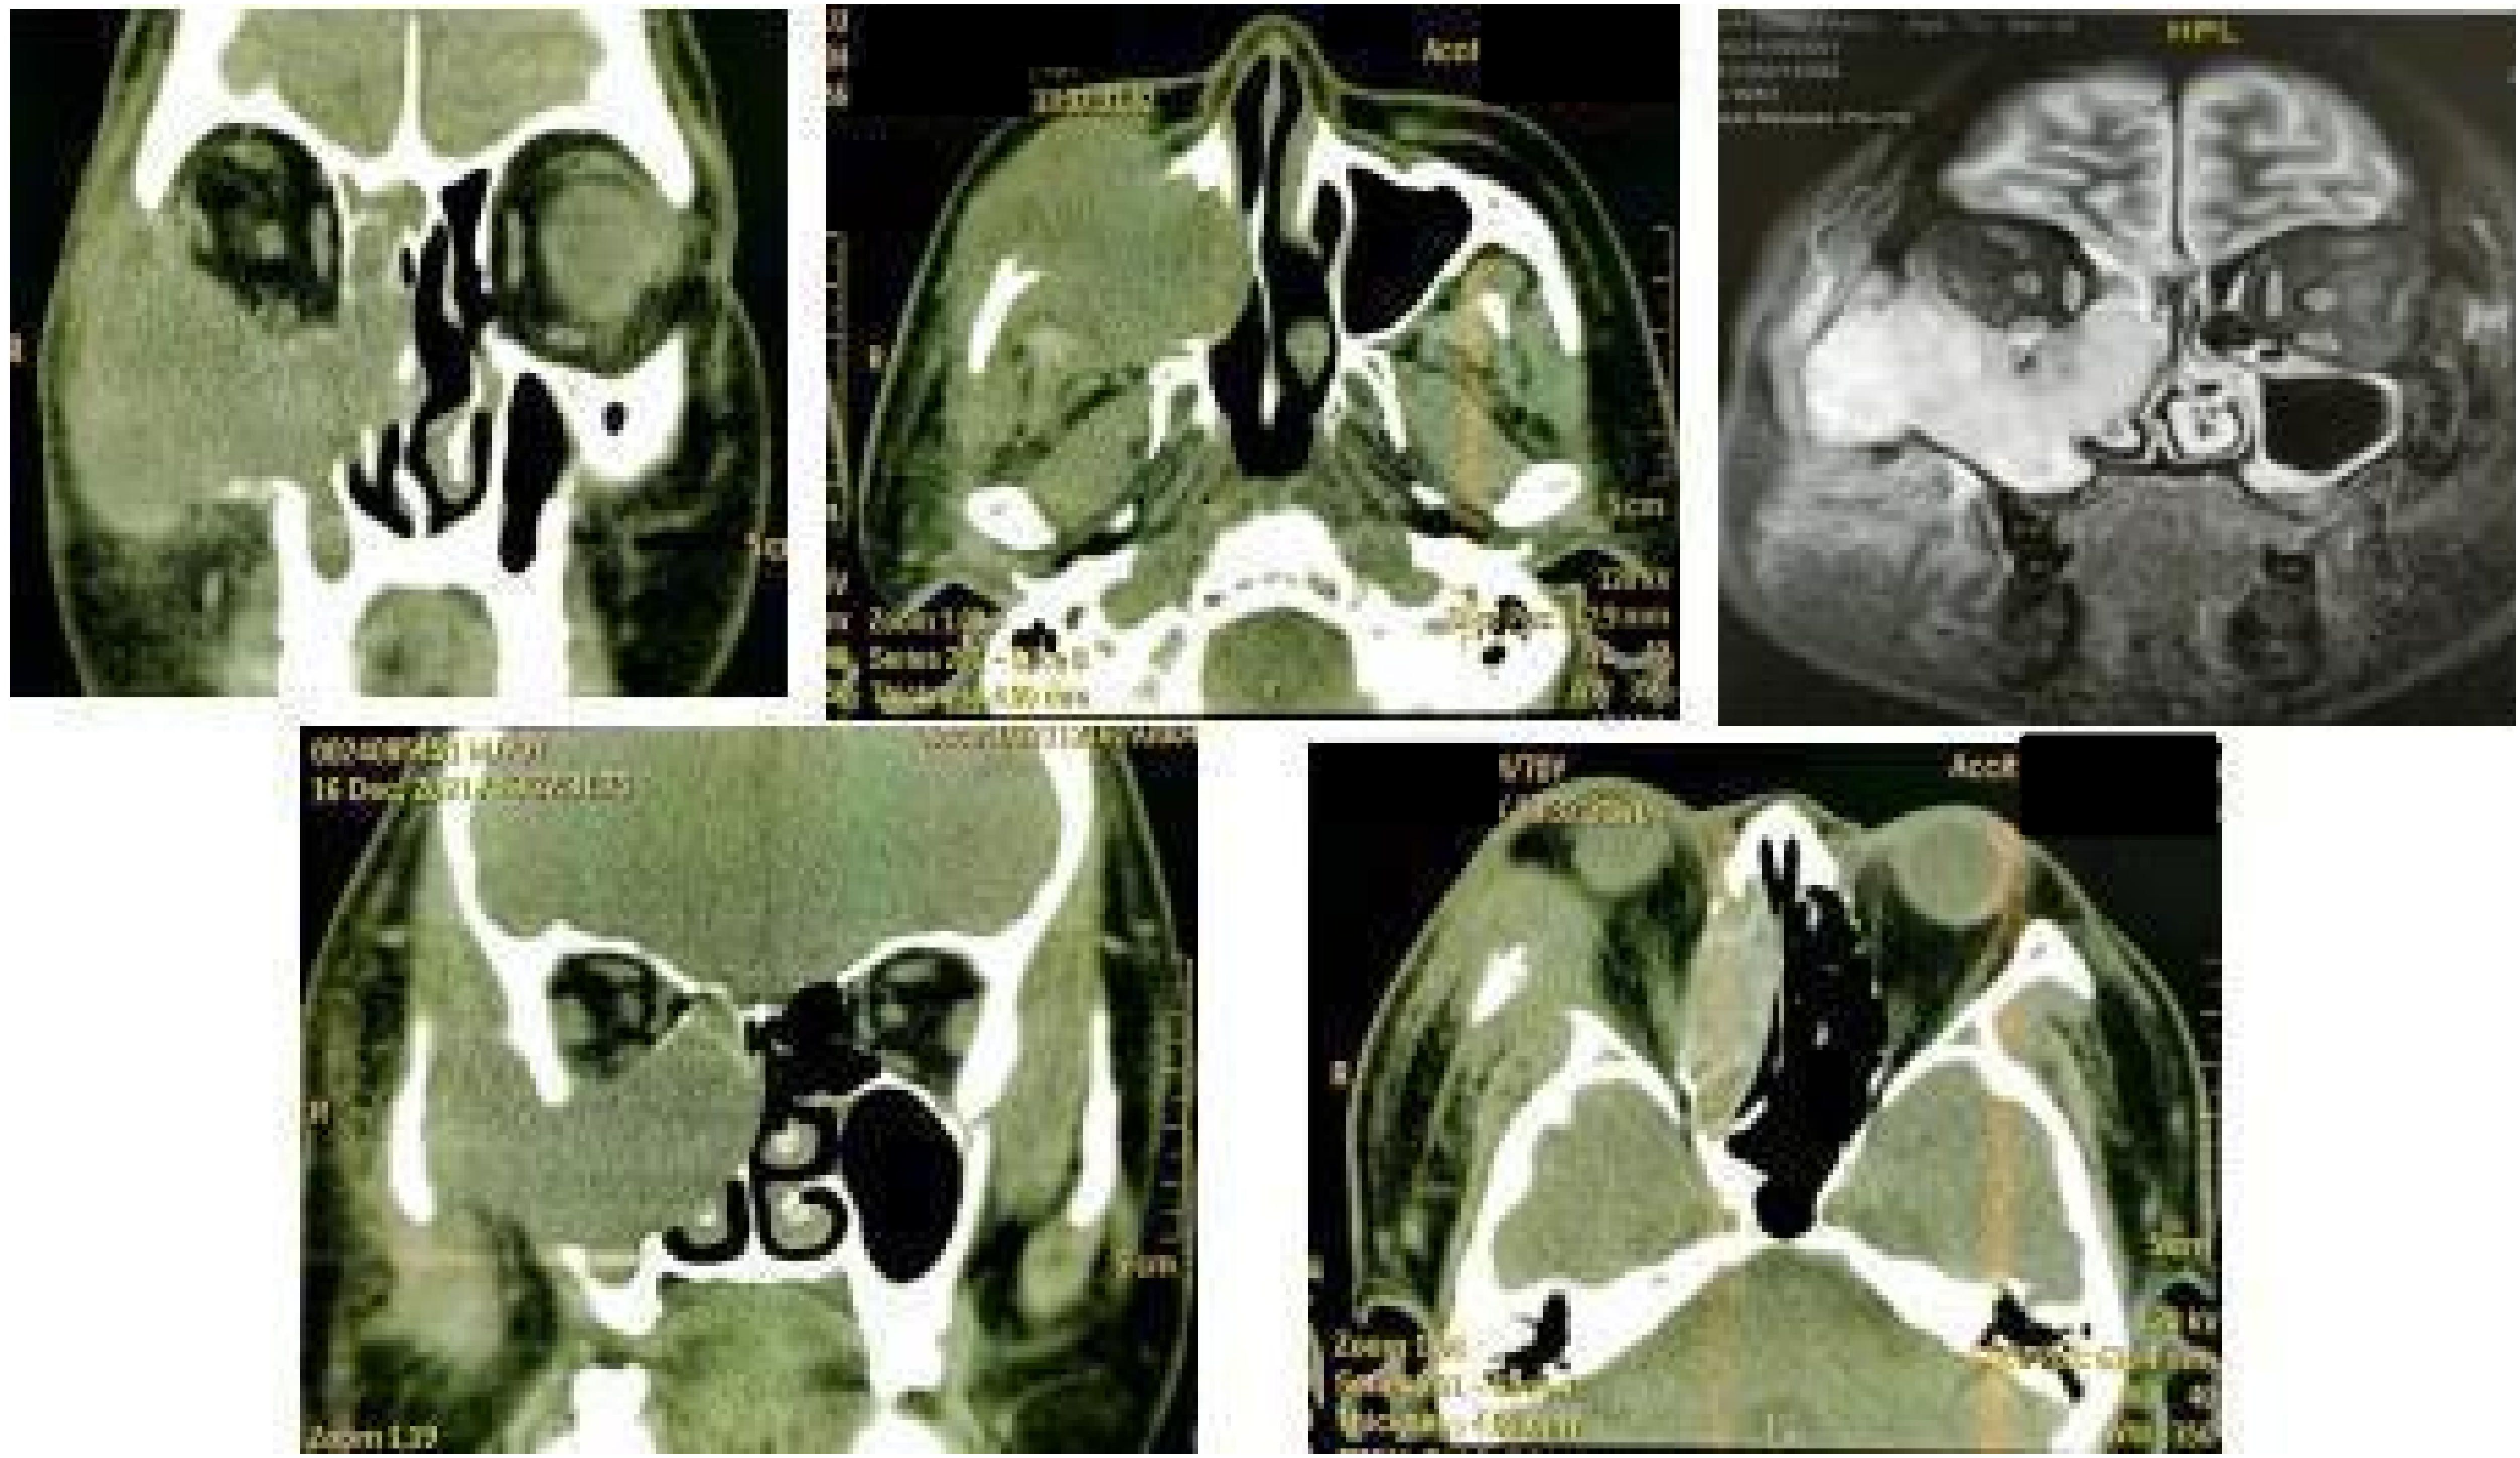

Preoperative 3D-CT and contrast-enhanced MRI showed a 5.5 cm mass in the right maxillary sinus involving the nasal cavity, ethmoid sinus, orbit, and pterygopalatine fossa, with destruction of the posterior maxillary wall, zygoma, and pterygoid process (Figure 1). Biopsy confirmed squamous cell carcinoma. Immunohistochemistry showed P16 and P40 positivity, Ki-67 >60%, and negative EBV.

Figure 1

3D-CT and MRI images of the space-occupying lesion in the right maxillary sinus.